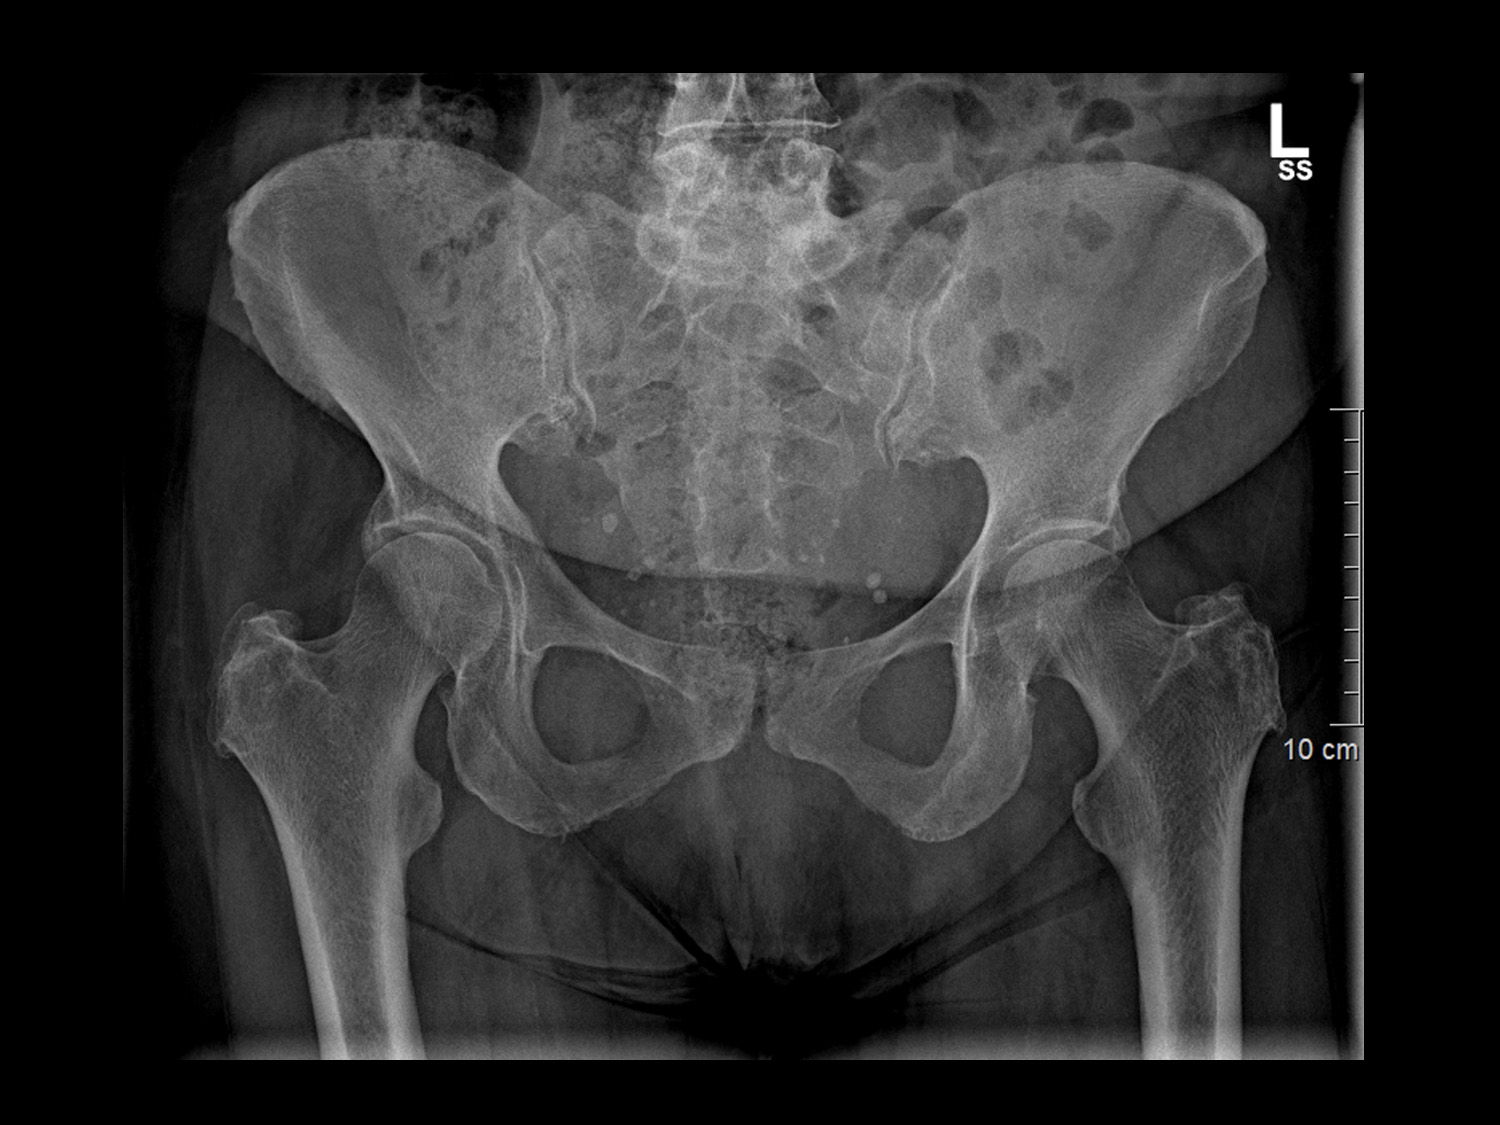

Röntgenuntersuchungen werden für eine Vielzahl von Zwecken eingesetzt, darunter die Diagnose von Knochenbrüchen, die Beurteilung von Organen wie Lunge, Herz und Verdauungstrakt sowie die Untersuchung von Weichteilgewebe auf Anzeichen von Verletzungen oder Erkrankungen. Die Röntgenbildgebung ist schnell, schmerzlos und nicht-invasiv und ermöglicht uns eine schnelle Diagnose und Behandlungsplanung.